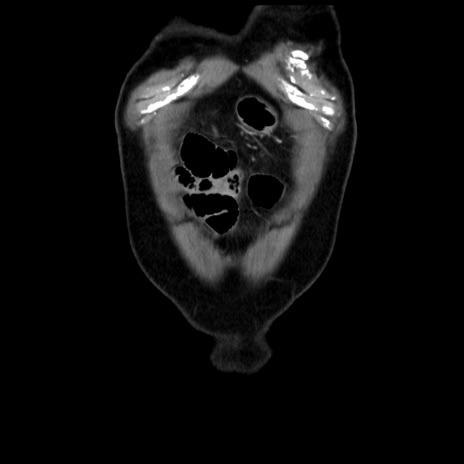

症例16(冠状断像)

横断像